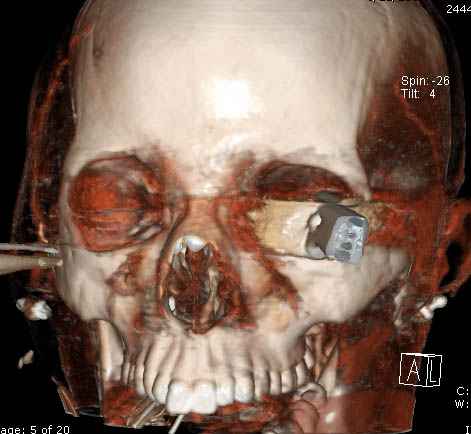

В своих выступлениях я рассказывал, что наши центры в мирное время по пенетрирующим травмам не уступает Ираку или Афганстану, и вот недавно к нам поступила больная 22 лет, травма "ножом в глаз" от бывшей подруги нынешнего "бой френда".

При поступлении в сознании, жаловалась на неприятные ощущения в глазнице.

По протоколу сделаны все необходимые исследования: рентген, ангиограмма с 3Д реконструкцией, где обнаружили что все жизненно важные сосуды не задеты, даже некоторые "сидят" изгибаясь на ноже.

Одним махом нож удалить не удалось, пришлось раскачать и потом двумя руками удалили нож. Рана без кровотечения, обработана и зашита.